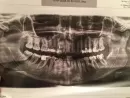

Обратилась к врачу с проблемой кровоточивости и воспаления дёсен. Сделали панорамный снимок, и врач сказал, что надо перелечить все пломбированные зубы, ставить коронки и только после этого лечить десны.

Хотелось бы знать Ваше мнение по этому поводу. Снимок прилагаю.

У Вас прогрессирует пародонтоз очень высокой степени. Протезирование не даст результатов. Во-первых, большое количество зубов необходимо удалить, при атрофии костной ткани ниже уровня бифуркации — тут уже ничего невозможно сделать.

Случай очень сложный, необходимо тщательно Вас осмотреть. Приезжайте ко мне на приём, мы попытаемся помочь Вам с наиболее профессиональной точки зрения.

Протезировать пока ничего не стоит. Я думаю, доктор не очень правильно с медицинской точки зрения понимает.